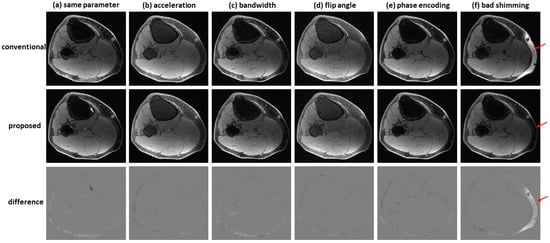

Figure 7 shows an example of water–fat separation from non-contrast-enhanced dual-echo images using a model trained with contrast-enhanced images. Even if the imaging parameters were slightly different from those adopted in contrast-enhanced studies (with an acceleration factor of 2, bandwidth of 83.3 kHz, flip angle of 25°, or phase encoding of 224), the predicted images had high fidelity to the reference images, indicating the proposed method has high potential to support flexible imaging parameters. When bad shimming was intentionally imposed (to generate highly inhomogeneous B 0 field), water/fat swaps that occurred in reference images were corrected in the predicted images.

Figure 7. Water–fat separation from non-contrast-enhanced dual-echo images using a model trained with contrast-enhanced images. The non-contrast-enhanced dual-echo images were acquired using (a) the same imaging parameters as those adopted in contrast-enhanced studies, (b) an acceleration factor of 2, (c) bandwidth of 83.3 kHz, (d) flip angle of 25°, and (e) phase encoding of 224. In these cases, the predicted images had high fidelity to the reference images. (f) When bad shimming was intentionally imposed, water/fat swaps that occurred in the reference image were corrected in the predicted image.